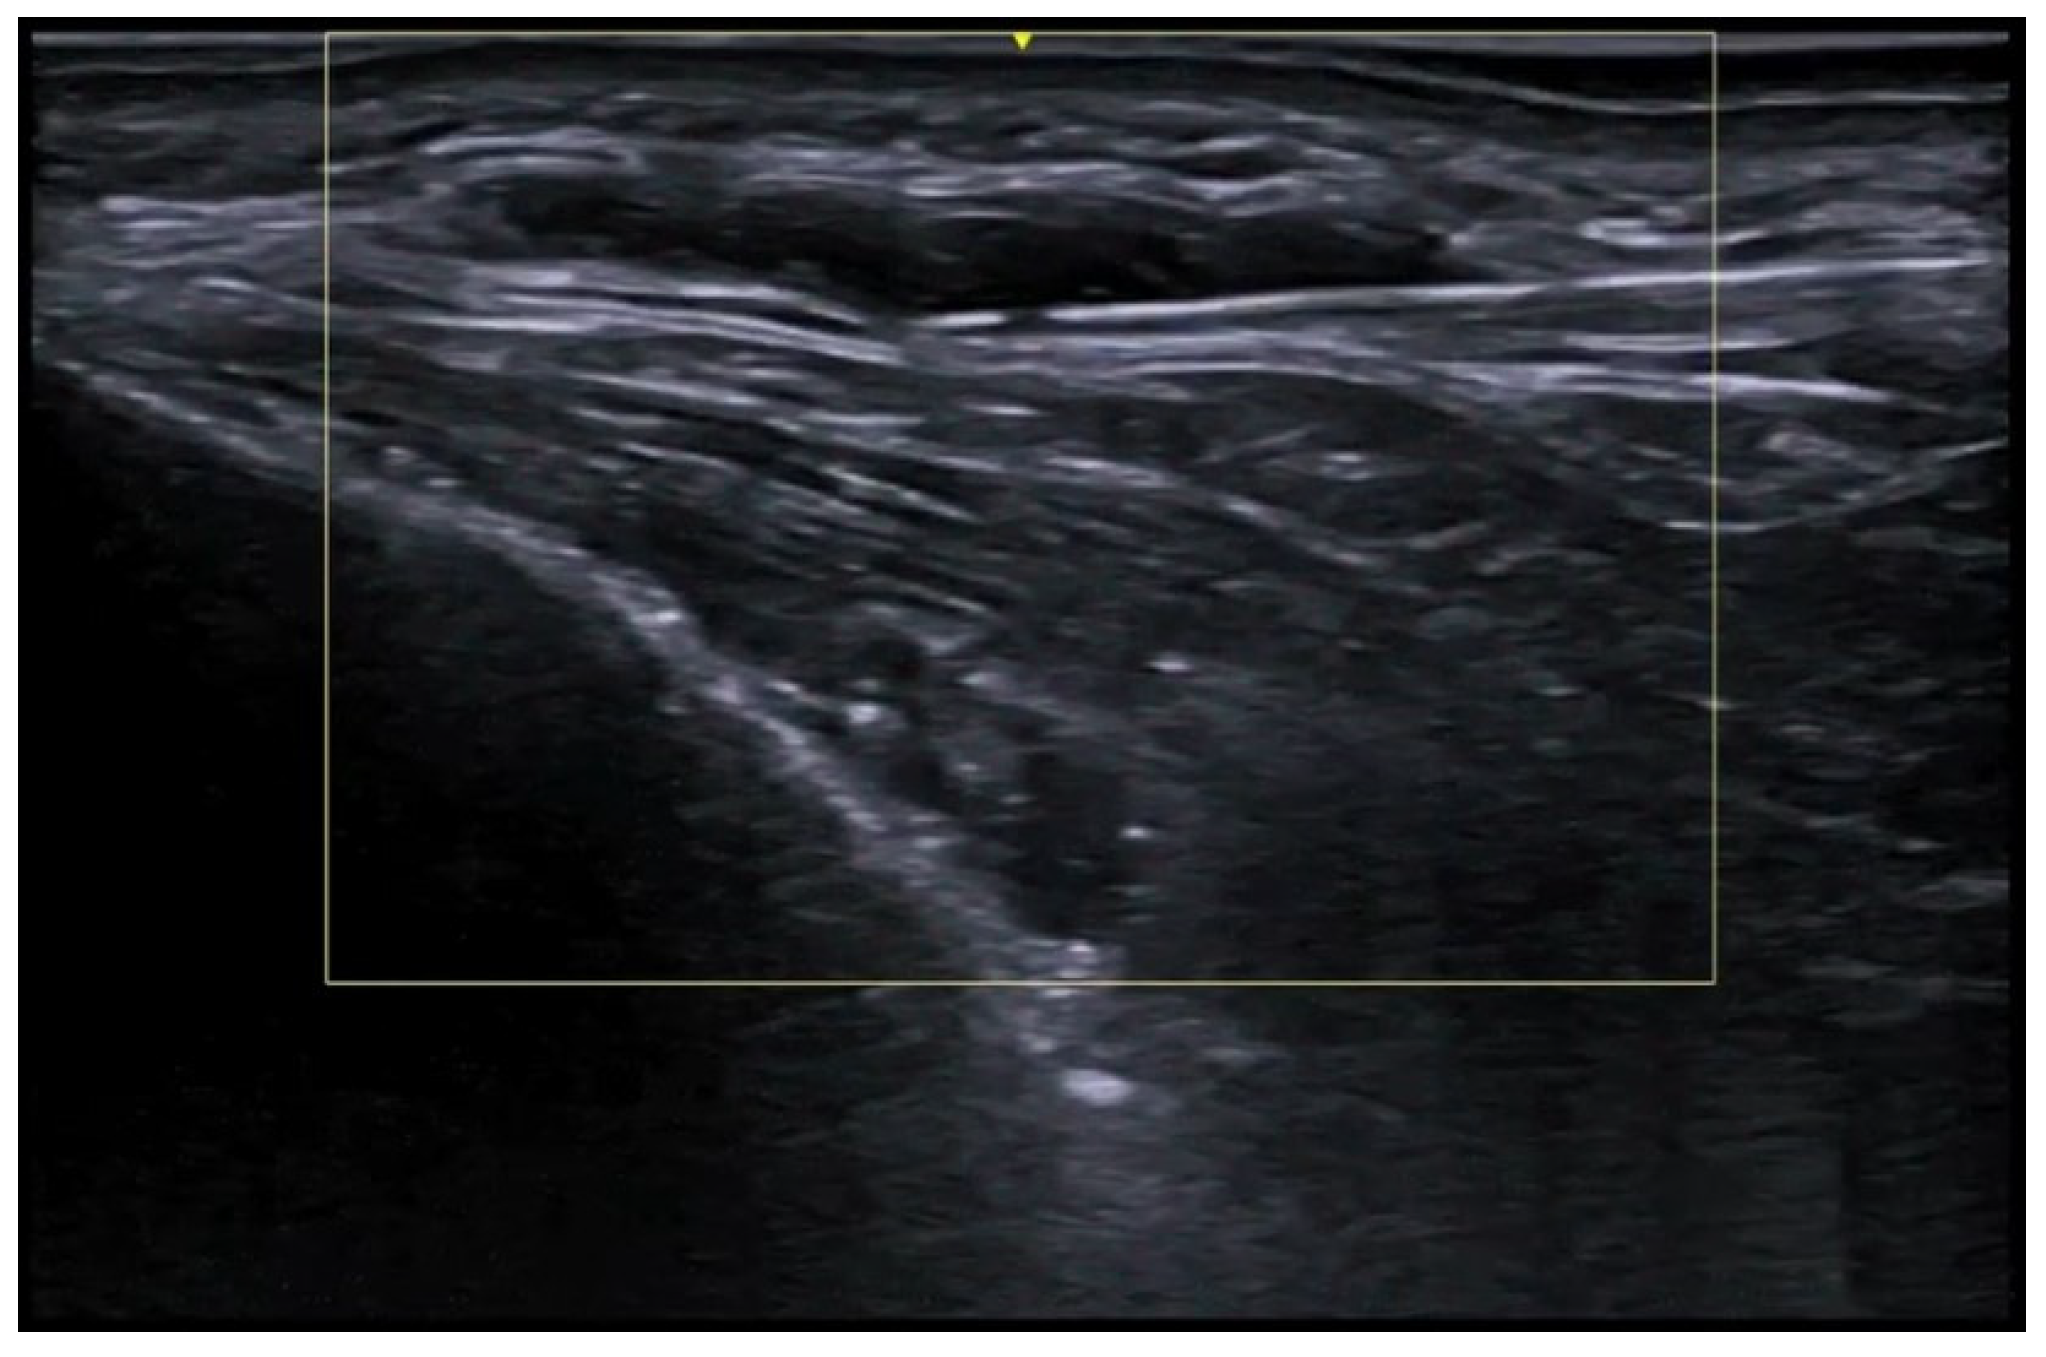

- Wortsman, X. Update on Ultrasound Diagnostic Criteria and New Ultrasound Severity and Activity Scorings of Hidradenitis Suppurativa: Modified SOS-HS and US-HSA. J. Ultrasound Med. 2024, 43, 207–213. [Google Scholar] [CrossRef] [PubMed]

- Mendes-Bastos, P.; Martorell, A.; Bettoli, V.; Matos, A.P.; Muscianisi, E.; Wortsman, X. The use of ultrasound and magnetic resonance imaging in the management of hidradenitis suppurativa: A narrative review. Br. J. Dermatol. 2023, 188, 591–600. [Google Scholar] [CrossRef]